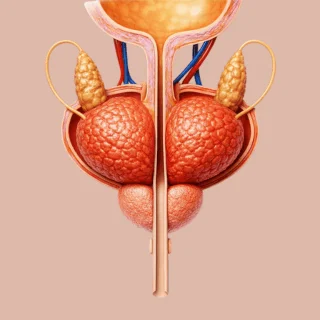

Prostatectomía

Cirugía para la extirpación total de la próstata y las vesículas seminales, indicada para el tratamiento del cáncer de próstata; así, se logra un manejo más preciso.